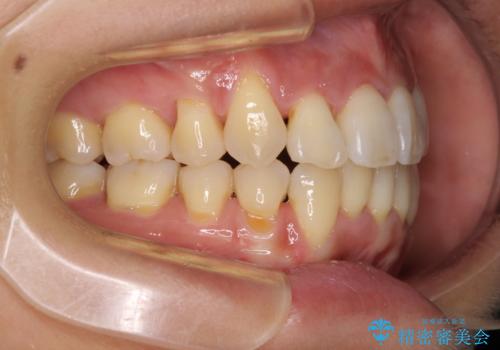

通常であれば、上下顎左右小臼歯各1歯の合計4本を抜歯しますが、歯肉退縮の著しい下顎前歯を抜歯して欲しいという患者様の強い希望により、上顎のみ左右小臼歯2歯を、下顎は前歯を1歯を抜歯することとしました。

抜歯する歯を変更したため奥歯の咬合はアンバランスとなりましたが、前歯は綺麗に整い、歯肉退縮も回避できました。